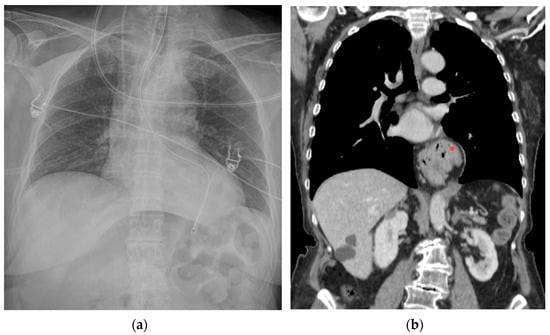

5.3. Ventricular Assistance Devices (VADs)

5.4. Impella